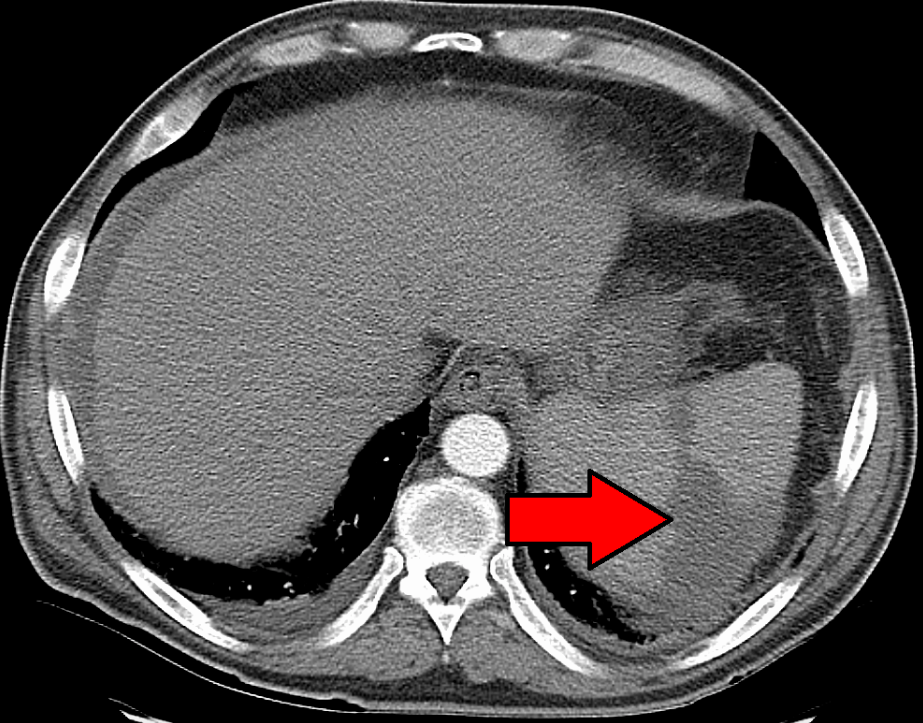

- Gold standard: CT abdomen with IV contrast

Will show segmental wedge shaped infarct towards hilum of the spleen. Whole spleen hypoattentuated if splenic artery occluded not a branch